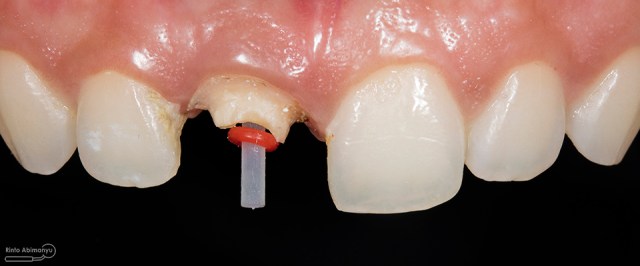

Untuk kunjungan pertama ini saya rencanakan melakukan perawatan saluran akar langsung pada dua gigi central… Saya pasang rubber dam untuk mengisolasi daerah kerja

Gigi 11 21 setelah dipasang rubber dam

Akses kamar pulpa dilakukan pada kedua gigi, dan penjajakan saluran menggunakan K-file nomer 10.. Kemudian pengukuran panjang kerja menggunakan apex locator Root ZX mini (Morita).. Preparasi saluran akar pada gigi insisiv tidak memerlukan waktu lama karena saluran akarnya yang sudah lebar, sehingga waktu yang terpakai lebih banyak untuk aktivasi irigasi, pada kasus ini saya menggunakan larutan irigasi NaOCl 5,25% dan diaktivasi menggunakan alat sonik waterpik dengan tip endoactivator….